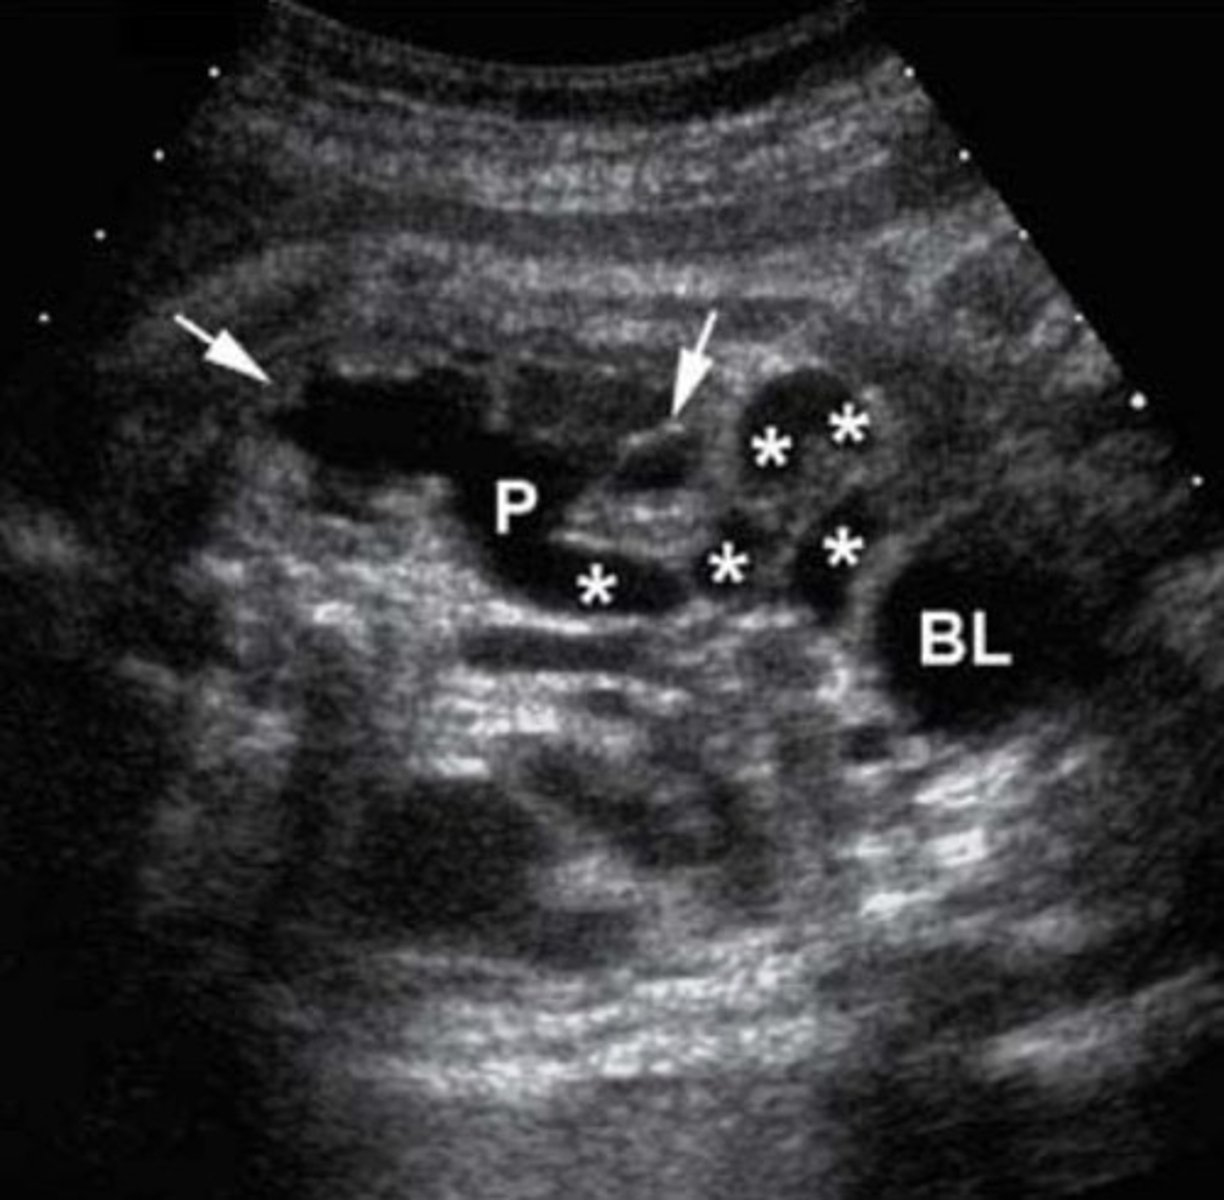

Posterior Urethral Valve Obstruction

Only in boys

Causes bilateral hydronephrosis

Thick bladder walls

Keyhole bladder appearance